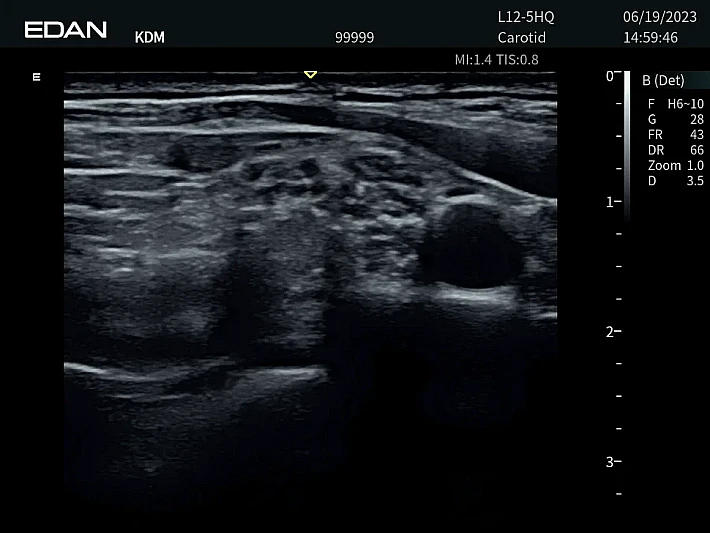

Медицинское оборудование и сервисное обслуживание